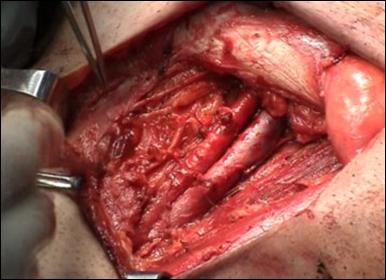

a. b.

Figura 17. Amputatia partiala de penis. a) schema anatomica; b) imagine intraoperatorie.